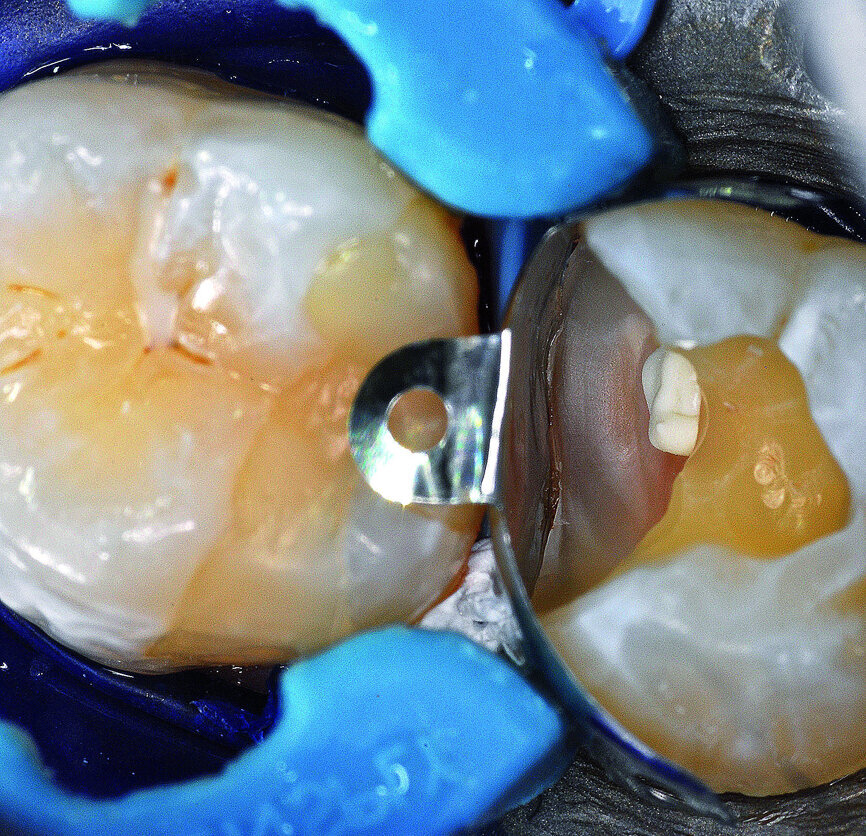

Pre-endodontic restoration

At the following visit, the tooth was anaesthetised, and a rubber dam placed. The temporary filling material was removed, revealing evidence of caries as indicated by caries indicator solution (Fig. 15). The caries was removed and the pulp was exposed (Fig. 16). A pre-endodontic restoration was performed using the Palodent V3 matrix system (Dentsply Sirona; Fig. 17) in combination with SDR bulk fill flowable resin (Dentsply Sirona) and ceram.x SphereTEC one composite resin (Dentsply Sirona; Fig. 18). After the pre-endodontic restoration, an access cavity was prepared and the canals were located under magnification.